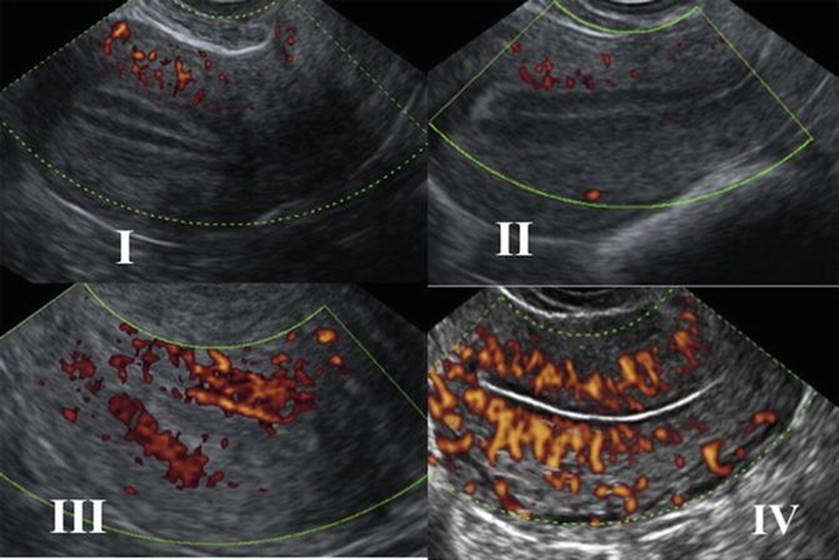

Using color Doppler, one can detect the vascularity of the ovarian stroma, follicular surface, and corpus luteum. PD analysis is an indirect indication of “health” of the follicle and possibly developmental competence of the corresponding oocyte. We know that initiation and maintenance of follicular growth depends on the development of perifollicular microvascular network and intrafollicular hypoxia can have an effect on mitochondrial function and chromosomal organization in oocytes and early embryos [13].

Thus, quantitative and qualitative assessments of perifollicular flow allow more accurate assessment of follicular competence (Fig. 2.14). Follicles that have more than 75 % of their surface perfused, ovarian stromal PSV of more than 10 cm/s, and RI of less than 0.4–0.48 contain mature oocytes of satisfactory quality and result in better grade of embryos.

Fig. 2.14

Perifollicular blood flow

Perifollicular Blood Flow (PFBF) Grading

· Grade 1: Blood flow (BF) <25 % of the follicle’s circumference

· Grade 2: BF ≥25 % but <50 %

· Grade 3: BF ≥50 % but <75 %

· Grade 4: BF ≥75 %

The perifollicular blood flow characteristics, measured by color Doppler images, are related to the intrafollicular oxygen content and vascular endothelial growth factor (VEGF) concentration, and oocytes from severely hypoxic follicles were associated with high frequencies of abnormalities in the organization of the chromosomes on the metaphase spindle [14].The best predictors of IVF outcome are the ovarian flow index (FI) using 3D ultrasound and power Doppler angiography (PDA) on the hCG day and the transfer of grade 1 embryos [14].

Follicles having a perifollicular blood flow of >50 % have increased oocyte retrieval rate with more number of mature oocytes with high fertilization rate and lower triploidy rates.